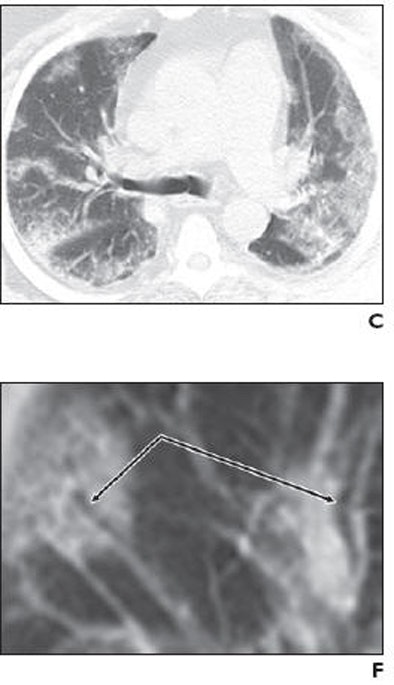

| Middle-aged man with no history of chronic pulmonary disease presented to emergency department with five-day history of fever, fatigue, nausea, diarrhea, and cough. Radiography and CT were performed. Unenhanced chest CT lung window images showed multifocal peripheral ground-glass opacities involving all lobes. Patient died on fifth day. Above: A, Chest radiograph obtained at clinical presentation shows peripheral opacities. B, Unenhanced chest CT lung window image shows apical patchy peripheral ground-glass opacities. D, Unenhanced chest CT lung window image reveals that lingula, right middle lobe, and both lower lobes show patchy, peripheral, rounded, peribronchial ground-glass opacities with air bronchograms. E, Unenhanced chest CT lung window image shows bilateral lung bases with ground-glass opacities still predominantly patchy at periphery, but more confluent ground-glass attenuation. Below: C, Unenhanced chest CT lung window image reveals that upper lobe and superior segments of both lower lobes show peripheral peribronchial ground-glass opacities. F, Magnified view of anterior segment of right upper lobe shows ground-glass opacity peripherally and air bronchograms (arrows). Images used with permission of the American Roentgen Ray Society. |

"Many of the opacities showed air bronchograms with normal-sized bronchial airways leading into each rounded ground-glass focus, and most large airways showed no significant wall thickening or plugging," Mollura et al wrote of the CT findings. "The ground-glass opacities were located throughout the upper and lower regions of all lobes in a peribronchovascular distribution. CT showed no evidence of a mosaic perfusion pattern, suggesting no localized air trapping or regional changes in blood flow."